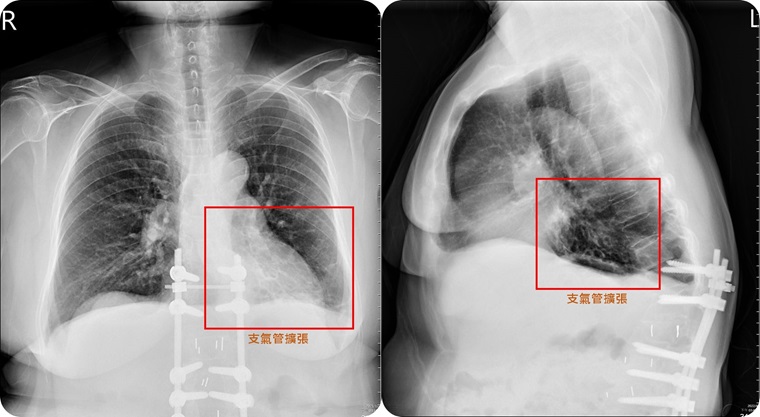

▲患者左下肺部的支氣管嚴重擴張,出現各種不適症狀。(圖/亞洲大學附屬醫院提供)

【NOW健康 連珮妤/台中報導】58歲簡阿姨從不抽菸,前幾個月卻突然久咳不停,痰液濃稠偏黃,且帶有血絲,吃藥後雖稍有改善,幾週後又變本加厲,近日還合併發燒,食慾也連帶受影響,就醫檢查後發現,左肺下方的支氣管變得粗大,裡面全被痰塞滿,確診為「支氣管擴張症」,幸好透過藥物及呼吸復健,症狀出現大幅改善,讓他擺脫「酷酷嫂」人生!